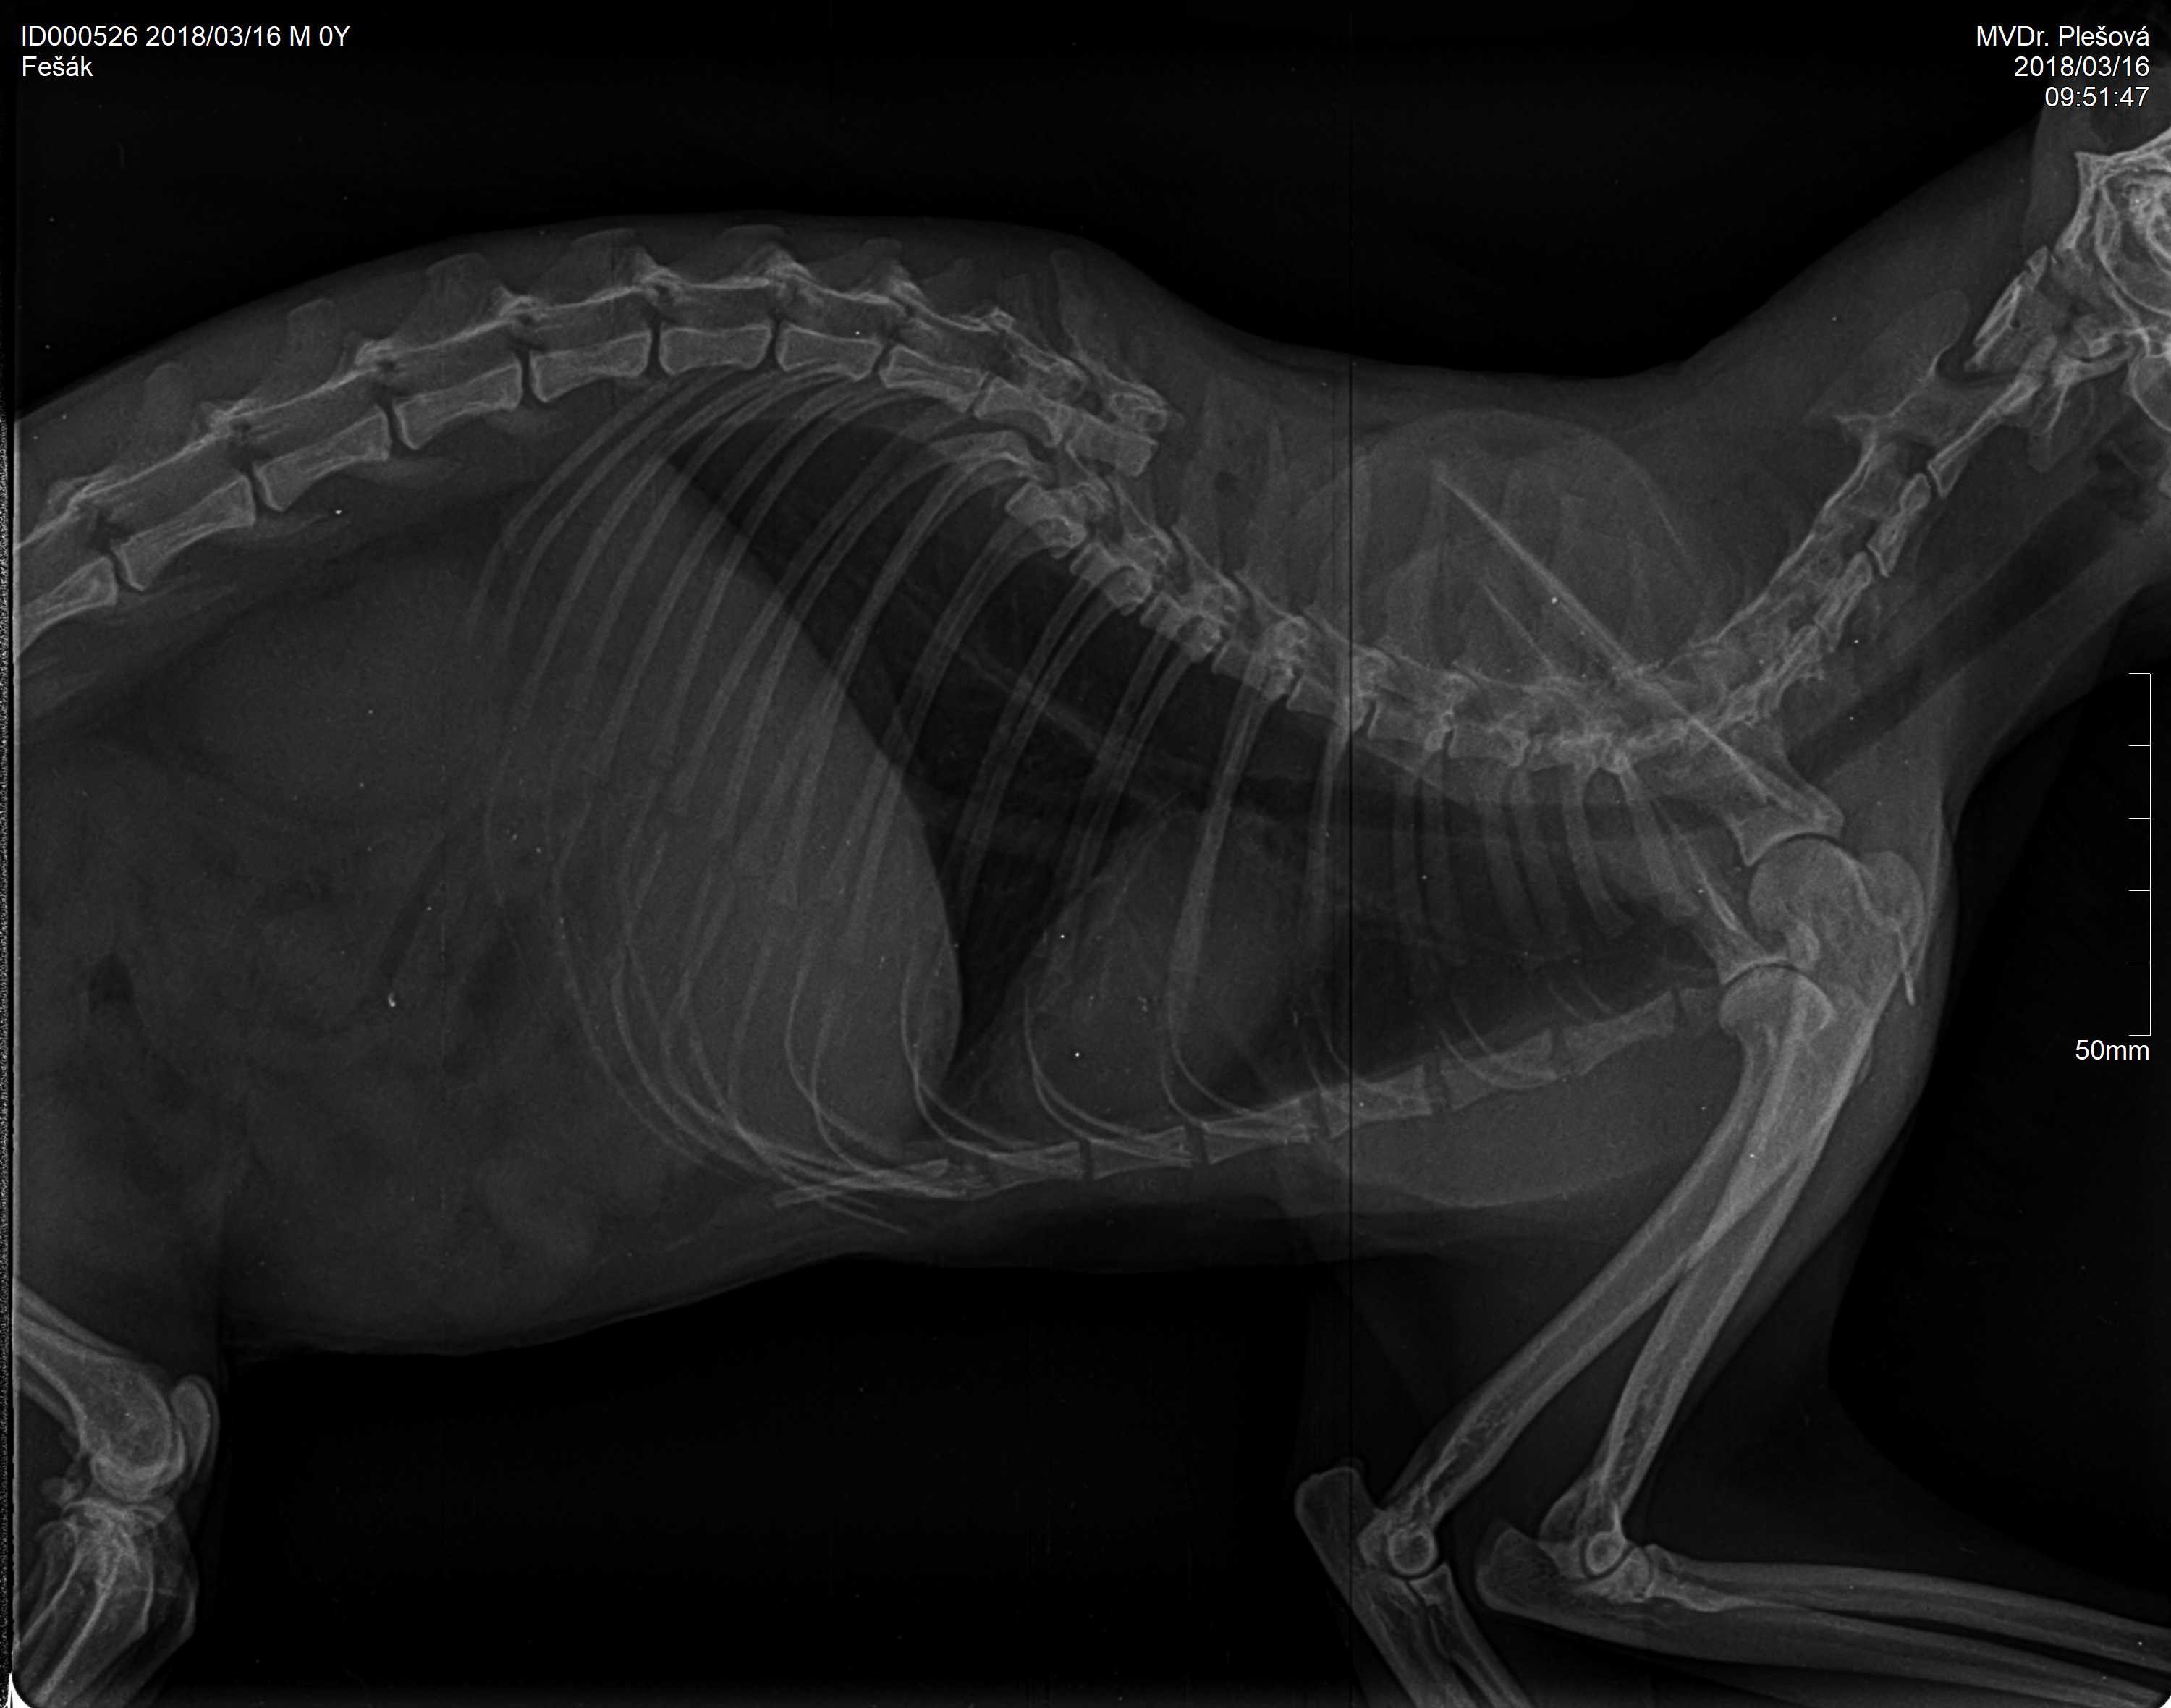

Fešák

Kocour

15.3.2018 - Dnes nám přivezla městská policie těžce zraněného nepohyblivého kocoura. Byl nalezen na Purkyňově ulici, na silnici, před budovou VaK. Bohužel se ukázalo, že zranění je neslučitelné se životem a kocourek byl uspán.